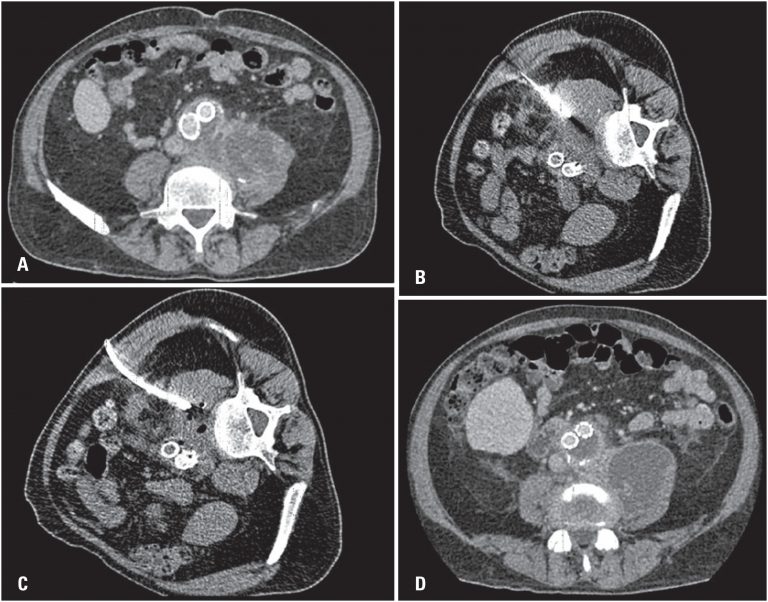

Chest computed tomography in the diagnosis of COVID-19 in patients with false negative RT-PCR

DOI: 10.31744/einstein_journal/2021AO6363

ABSTRACT Objective To evaluate the role of chest computed tomography in patients with COVID-19 who presented initial negative result in reverse transcriptase-polymerase chain reaction (RT-PCR). Methods A single-center, retrospective study that evaluated 39 patients with negative RT-PCR for COVID-19, who underwent chest computed tomography and had a final clinical or serological diagnosis of COVID-19. The visual tomographic classification was evaluated according to the Consensus of the Radiological Society of North America and software developed with artificial intelligence for automatic detection […]

Keywords: Coronavirus infections; Reverse transcriptase polymerase chain reaction; Tomography, x-ray computed